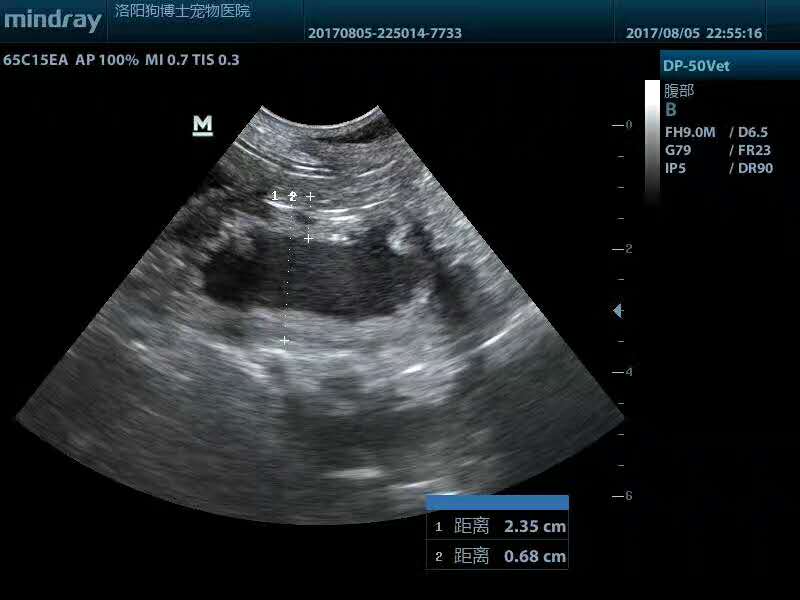

子宮蓄膿手術(shù)摘除:秋田犬,歡歡,9歲,母,未絕育,近期腹圍持續(xù)增大,昨日從***大量流出黃白色分泌物,主人懷疑即將分娩,來醫(yī)院檢查后,確診為子宮蓄膿,且高燒40.2度,病情危急,遂實施子宮卵巢摘除術(shù),手術(shù)順利。PS:再次提醒,不以繁育為目的的養(yǎng)寵,應(yīng)盡早絕育,能大大降低子宮蓄膿、乳腺腫瘤、卵巢囊腫等病的發(fā)病率,洛陽狗博仕寵物醫(yī)院。